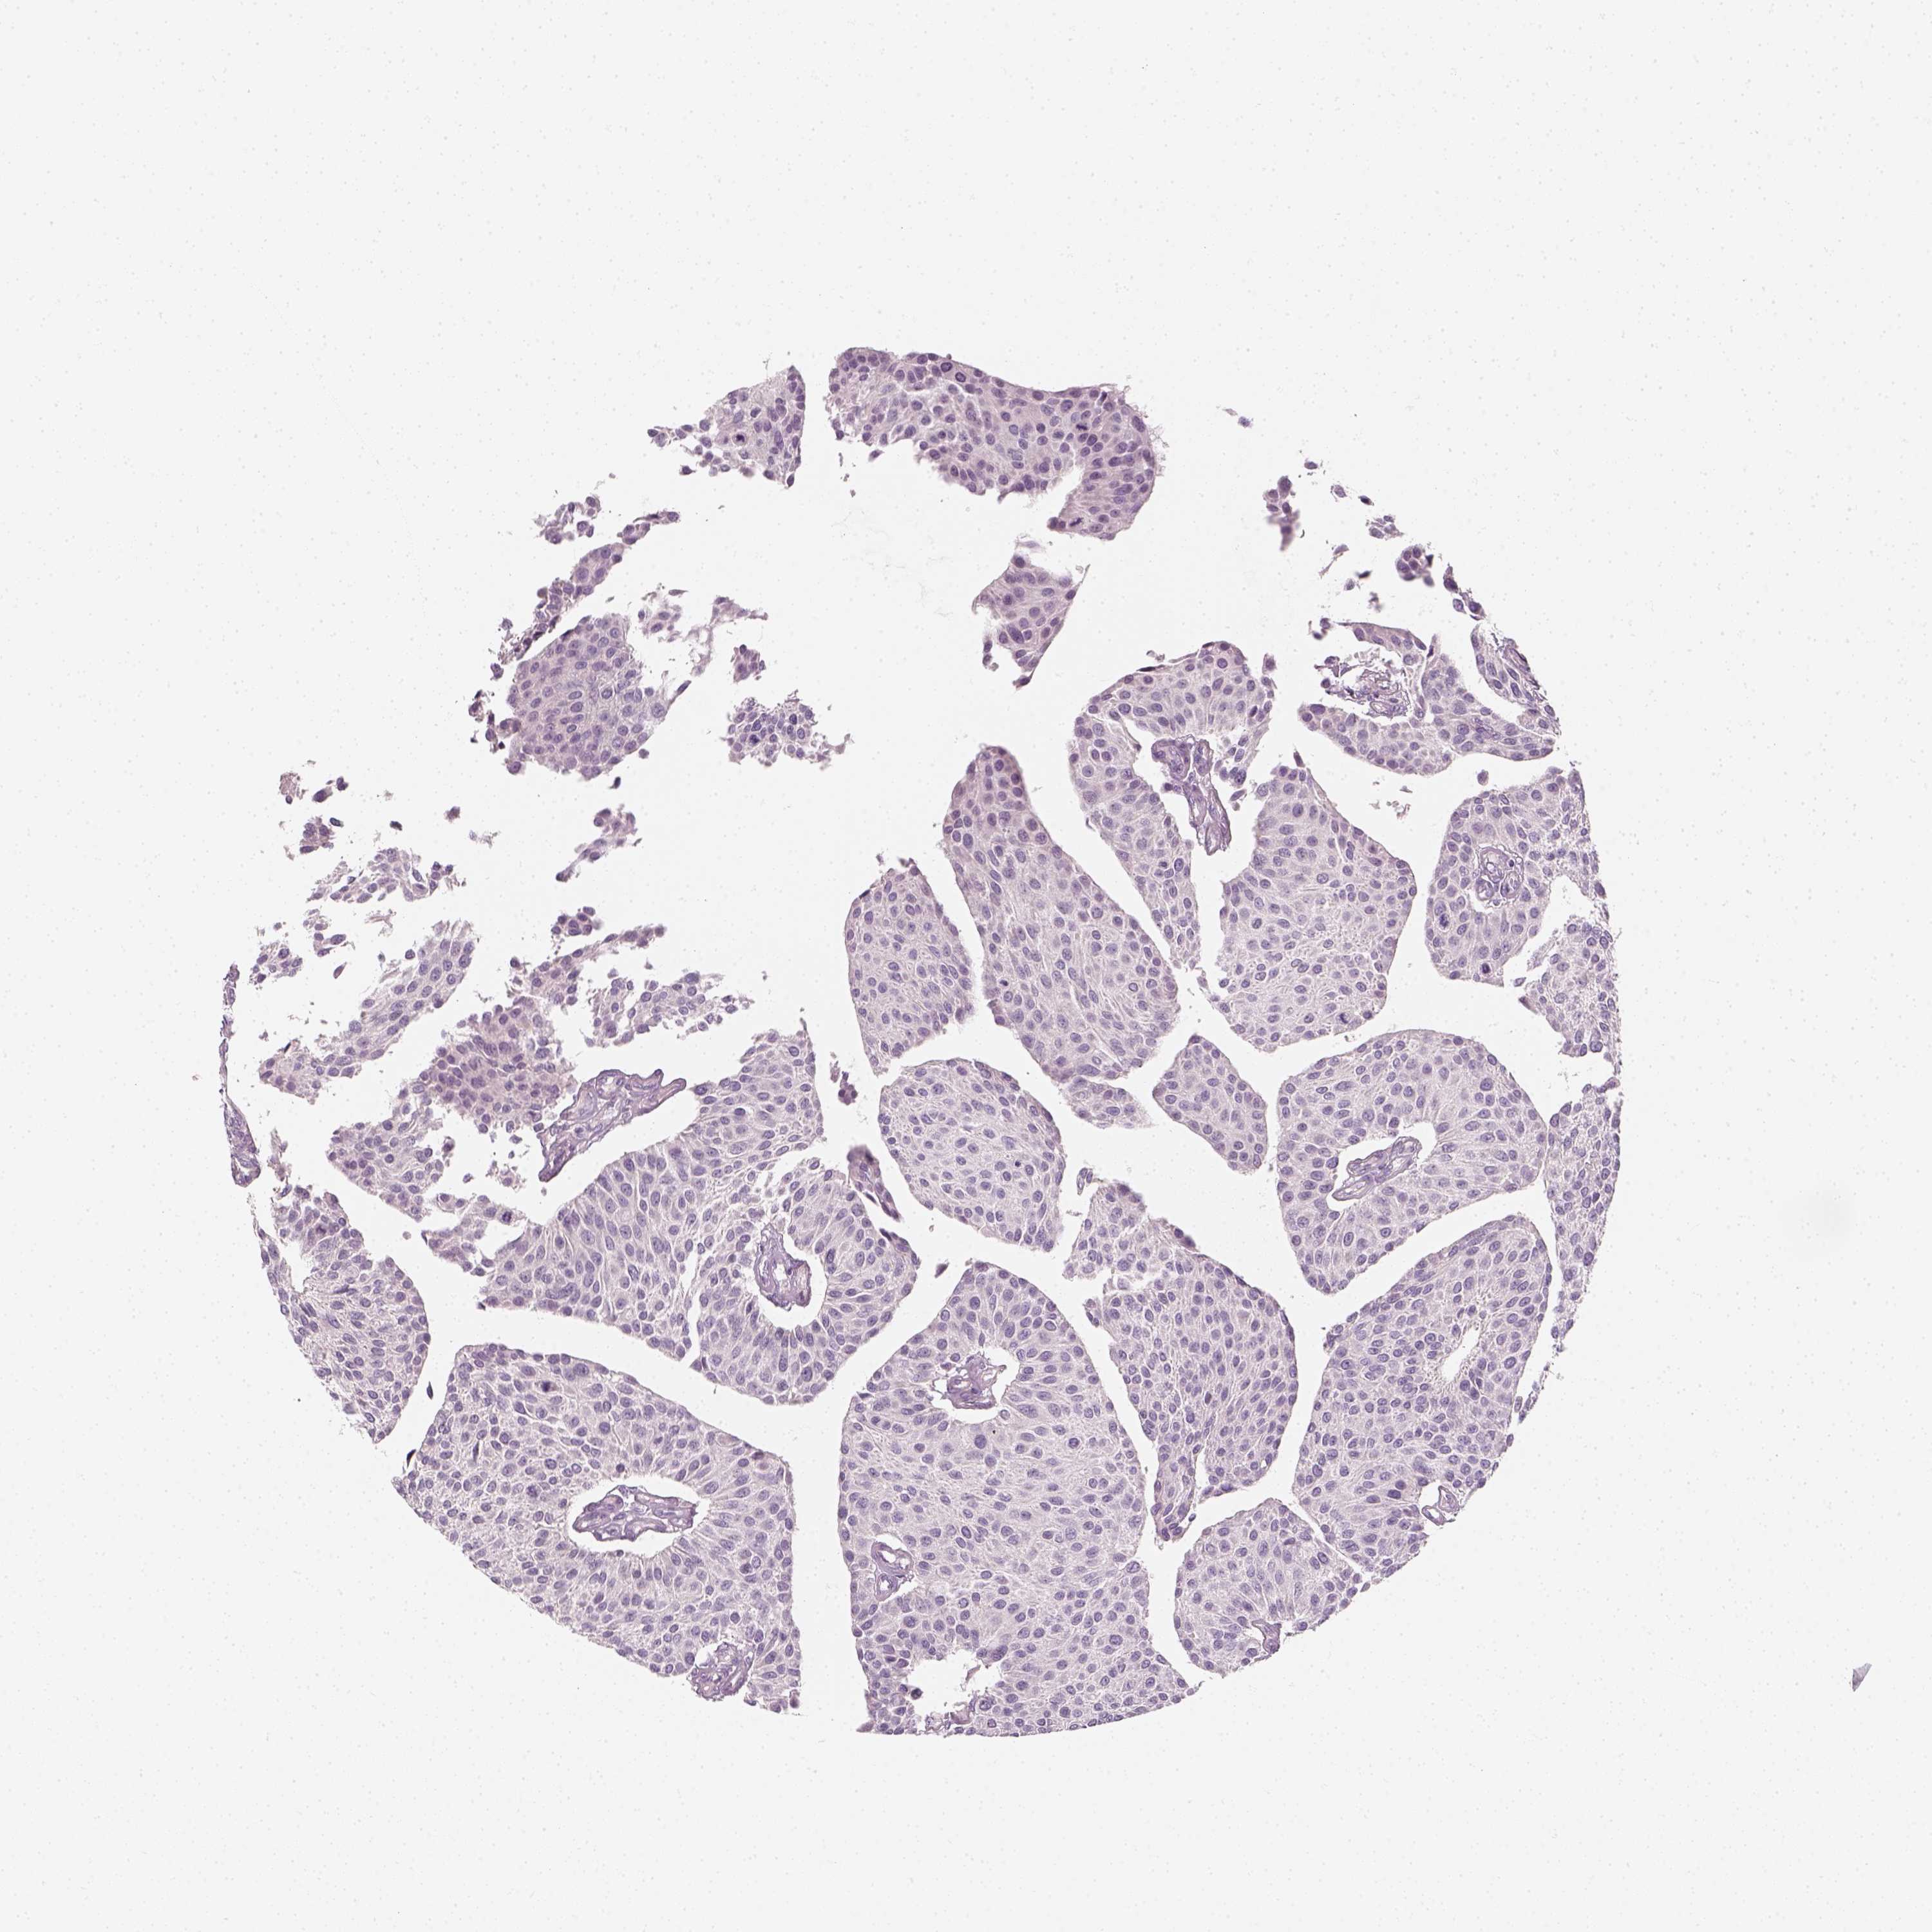

UROTHELIAL CANCER - Protein expressioni

A mouse-over function shows sample information and annotation data. Click on an image to view it in a full screen mode. Samples can be filtered based on level of antibody staining by selecting one or several of the following categories: high, medium, low and not detected. The assay and annotation is described here.

Antibody stainingi

Antibody staining in the annotated cell types in the current human tissue is reported as not detected, low, medium, or high, based on conventional immunohistochemistry profiling in selected tissues. This score is based on the combination of the staining intensity and fraction of stained cells.

Each image is clickable and will lead to virtual microscopy that enables deeper exploration of all samples and also displays staining intensity scores, fraction scores and subcellular localization as well as patient and tissue information for each sample.

Antibody HPA045153

Antibody CAB080138

Urothelial carcinoma, High grade

Urothelial carcinoma, NOS

Urothelial carcinoma, Low grade